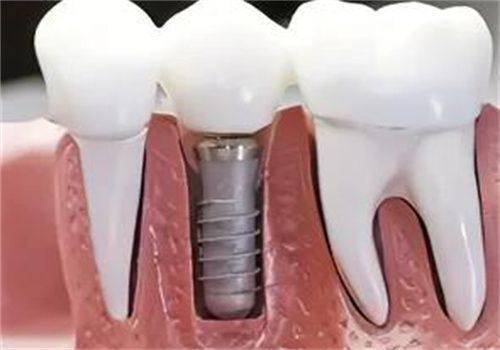

材质因素对种植牙寿命的影响

种植体和牙冠材料的质量对种植牙的使用寿命起着关键作用。高质量的材料能提供更长久的使用成效。像钛合金和陶瓷等材质就特别不错。钛合金具有良好的耐磨性和耐腐蚀性,而且生物相容性也良好,能与人体组织更好地融合,减少排异反应,从而延长种植牙的使用寿命。陶瓷材料则美观度高,在口腔中比较自然,同时也有较好的耐磨性。所以,在选择种植牙材料时,不要只看价格,更要关注其质量和性能,这样才能为种植牙的长久使用打下基础。